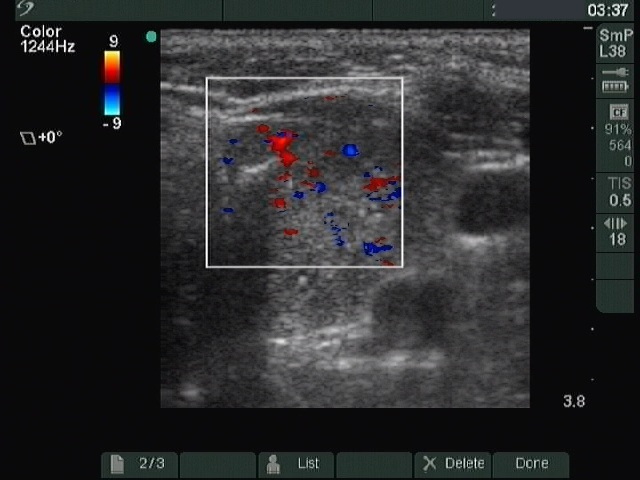

Left lobe, transverse scan, color Doppler mod. The lesion presents intranodular blood flow.